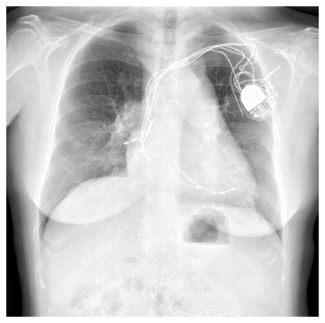

A 59-year-old man was referred to our institution for potential MitraClip (Abbott Vascular) therapy after he was found to have severe mitral regurgitation (MR) seen on transthoracic echocardiography. He had a history of coronary artery disease and functional MR, and underwent coronary artery bypass grafting and mitral annuloplasty (28 mm CG Future; Medtronic Inc.) 4 years prior at an outside institution. A permanent pacemaker was also implanted for advanced atrioventricular block. The procedure was complicated by a methicillin-resistant  staph aureus sternal wound infection requiring multiple debridements and wound vacuum drainage for 1 year. There was no documented bacteremia at that time. Three years later, he had several admissions for decompensated heart failure, volume overload, and pulmonary edema without angina pectoris. Transthoracic echocardiogram revealed left ventricular (LV) ejection fraction of 55%, severe MR with 2 distinct regurgitant jets, and an estimated right ventricular pulmonary systolic pressure of 60 mm Hg. Subsequent transesophageal echocardiography (TEE) demonstrated a dilated mitral annulus with the septal-lateral dimension measuring 36 mm. There was significant dehiscence of the annuloplasty ring from the posterior annulus and focal dehiscence at the right fibrous trigone, with a resultant 6 x 8 mm perforation at the base of the anterior mitral leaflet (Figure 1). There was 4+ MR through the mitral leaflet perforation and 1+ central MR. There was trivial regurgitation through the posterior dehiscence (Figure 2). After referral to our center, 3.5 years after the original operation, several blood cultures drawn on different days were negative and an erythrocyte sedimentation rate was normal. Angiography demonstrated occluded vein grafts to the left circumflex and right coronary arteries with severe native diffuse disease not amenable to percutaneous or surgical revascularization. The left internal mammary artery graft to left anterior descending artery was patent. In view of his related comorbidities and prior sternal wound infection, percutaneous repair of the anterior mitral leaflet perforation was performed.

staph aureus sternal wound infection requiring multiple debridements and wound vacuum drainage for 1 year. There was no documented bacteremia at that time. Three years later, he had several admissions for decompensated heart failure, volume overload, and pulmonary edema without angina pectoris. Transthoracic echocardiogram revealed left ventricular (LV) ejection fraction of 55%, severe MR with 2 distinct regurgitant jets, and an estimated right ventricular pulmonary systolic pressure of 60 mm Hg. Subsequent transesophageal echocardiography (TEE) demonstrated a dilated mitral annulus with the septal-lateral dimension measuring 36 mm. There was significant dehiscence of the annuloplasty ring from the posterior annulus and focal dehiscence at the right fibrous trigone, with a resultant 6 x 8 mm perforation at the base of the anterior mitral leaflet (Figure 1). There was 4+ MR through the mitral leaflet perforation and 1+ central MR. There was trivial regurgitation through the posterior dehiscence (Figure 2). After referral to our center, 3.5 years after the original operation, several blood cultures drawn on different days were negative and an erythrocyte sedimentation rate was normal. Angiography demonstrated occluded vein grafts to the left circumflex and right coronary arteries with severe native diffuse disease not amenable to percutaneous or surgical revascularization. The left internal mammary artery graft to left anterior descending artery was patent. In view of his related comorbidities and prior sternal wound infection, percutaneous repair of the anterior mitral leaflet perforation was performed.

Initially, right heart catheterization was performed that demonstrated pulmonary arterial pressure of 40/20 with mean pulmonary capillary wedge pressure of 18 mm Hg and V waves up to 22 mm Hg. Simultaneously, left heart catheterization revealed LV end diastolic pressure of 17 mm Hg, ruling out mitral stenosis. A BRK needle (St. Jude Medical) was used to perform transseptal puncture under echocardiographic guidance and a Mullins transseptal sheath (Medtronic Inc.) was advanced through the interatrial septum in a superior location within the fossa ovalis. Intravenous heparin was given at this point. Mean left atrial pressure was recorded at 18 mm Hg with prominent V waves up to 40 mm Hg. The Mullins sheath was then removed and a medium curl Agilis NxT catheter (11.5 Fr outer diameter, 8.5 Fr inner diameter, St. Jude Medical) was advanced into the left atrium and directed toward the base of the anterior mitral leaflet. Through the Agilis catheter, an 8 Fr EBU 3.75 guiding catheter (Medtronic Inc.) was then advanced to its tip. Another multipurpose catheter was then nested through the guiding catheter using a triple telescoping “mother and child” approach. An exchange-length 0.035˝ angled Glidewire (Terumo Medical Corporation) was then advanced through the leaflet perforation using three-dimensional TEE guidance in an antegrade fashion. Over the Glidewire, the multipurpose catheter was passed through the defect into the LV apex. The Glidewire was then exchanged for an Amplatz Superstiff wire (Boston Scientific), over which the EBU guiding catheter was advanced in the LV cavity (Figure 2). Once the guiding catheter was appropriately positioned in the LV midcavity, the multipurpose catheter as well as the stiff wire were removed. Then, a 5 mm Amplatzer atrial septal occluder was loaded into the guiding catheter and deployed successfully to the anterior mitral leaflet perforation under TEE guidance (Figure 3). On color Doppler, there was no residual MR through the leaflet perforation and only 1+ functional (central) MR with excellent device stability (Figures 1 and 4). The anterior mitral leaflet had preserved mobility and there was no obstruction of the LVOT (Figure 4). Mean left atrial pressure after the repair was 15 mm Hg with diminished V waves. Final transmitral gradient was 4 mm Hg with mitral valve area of 2.5 cm2. Procedural fluoroscopy time was 27 minutes. The postprocedure course was uneventful and the patient was discharged on aspirin and clopidogrel on postprocedure day 1. At 1-month follow-up, he was in New York Heart Association functional class I. He developed transient mild hemolytic anemia, which did not require transfusion. On follow-up echocardiogram, there was no residual MR through the defect and only 1+ central MR.

Initially, right heart catheterization was performed that demonstrated pulmonary arterial pressure of 40/20 with mean pulmonary capillary wedge pressure of 18 mm Hg and V waves up to 22 mm Hg. Simultaneously, left heart catheterization revealed LV end diastolic pressure of 17 mm Hg, ruling out mitral stenosis. A BRK needle (St. Jude Medical) was used to perform transseptal puncture under echocardiographic guidance and a Mullins transseptal sheath (Medtronic Inc.) was advanced through the interatrial septum in a superior location within the fossa ovalis. Intravenous heparin was given at this point. Mean left atrial pressure was recorded at 18 mm Hg with prominent V waves up to 40 mm Hg. The Mullins sheath was then removed and a medium curl Agilis NxT catheter (11.5 Fr outer diameter, 8.5 Fr inner diameter, St. Jude Medical) was advanced into the left atrium and directed toward the base of the anterior mitral leaflet. Through the Agilis catheter, an 8 Fr EBU 3.75 guiding catheter (Medtronic Inc.) was then advanced to its tip. Another multipurpose catheter was then nested through the guiding catheter using a triple telescoping “mother and child” approach. An exchange-length 0.035˝ angled Glidewire (Terumo Medical Corporation) was then advanced through the leaflet perforation using three-dimensional TEE guidance in an antegrade fashion. Over the Glidewire, the multipurpose catheter was passed through the defect into the LV apex. The Glidewire was then exchanged for an Amplatz Superstiff wire (Boston Scientific), over which the EBU guiding catheter was advanced in the LV cavity (Figure 2). Once the guiding catheter was appropriately positioned in the LV midcavity, the multipurpose catheter as well as the stiff wire were removed. Then, a 5 mm Amplatzer atrial septal occluder was loaded into the guiding catheter and deployed successfully to the anterior mitral leaflet perforation under TEE guidance (Figure 3). On color Doppler, there was no residual MR through the leaflet perforation and only 1+ functional (central) MR with excellent device stability (Figures 1 and 4). The anterior mitral leaflet had preserved mobility and there was no obstruction of the LVOT (Figure 4). Mean left atrial pressure after the repair was 15 mm Hg with diminished V waves. Final transmitral gradient was 4 mm Hg with mitral valve area of 2.5 cm2. Procedural fluoroscopy time was 27 minutes. The postprocedure course was uneventful and the patient was discharged on aspirin and clopidogrel on postprocedure day 1. At 1-month follow-up, he was in New York Heart Association functional class I. He developed transient mild hemolytic anemia, which did not require transfusion. On follow-up echocardiogram, there was no residual MR through the defect and only 1+ central MR.